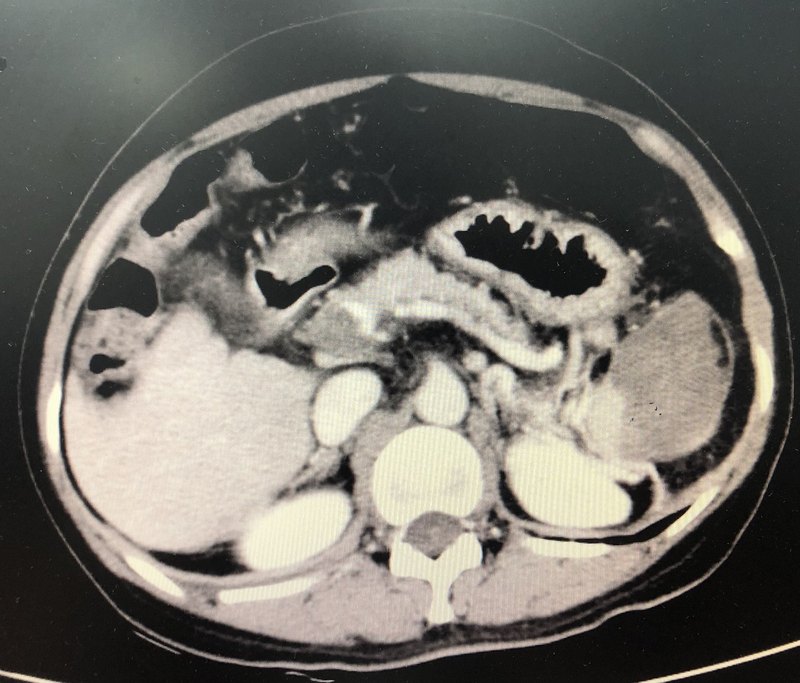

抗凝聯(lián)合經(jīng)腸系膜上動(dòng)脈置管溶栓治療彌漫門脈血栓案例分享

患者中年男性,因?yàn)楦雇锤姑?天,加重1天到我院急診科求診,急診超聲及ct提示門脈左右支主干、脾靜脈及腸系膜上靜脈血栓形成。門脈左支血栓形成。門脈右支血栓形成。門脈主干及脾靜脈血栓形成。腸系膜上靜脈血栓形成??鼓惶旌蟾雇窗Y狀稍有緩解,2023.9.26行經(jīng)腸系膜上動(dòng)脈置管溶栓治療,尿激酶25萬U,q6h,2023.10.1拔管,繼續(xù)經(jīng)靜脈溶栓治療,尿激酶25萬U,q8h,患者肝素過敏,溶栓期間利伐沙班15mg,bid。10月7復(fù)查ct,門脈脾靜脈及腸系膜上靜脈血栓變化不明顯,但是患者腹痛腹脹癥狀基本消失,可正常進(jìn)食及排便,給予出院繼續(xù)口服利伐沙班抗凝治療。2023.11.14患者復(fù)查ct,提示門靜脈、脾靜脈及腸系膜上靜脈血栓大部分消失,門脈主干仍然殘存少許血栓。門脈左支血栓基本消失。門脈右支血栓基本消失。腸系膜上靜脈血栓基本消失。脾靜脈血栓基本消失。門脈主干似有少許血栓殘余。繼續(xù)密切觀察,繼續(xù)抗凝治療,利伐沙班20毫克,qd。點(diǎn)評(píng):門脈血栓臨床多見,治療方案選擇也存在一定的爭議,我們既往采取抗凝治療聯(lián)合經(jīng)腸系膜上動(dòng)脈置管溶栓治療不同程度門脈血栓患者均取得良好效果。此患者就診時(shí)候血栓負(fù)荷極大且腹脹腹痛癥狀明顯,隨時(shí)有腸壞死風(fēng)險(xiǎn),采取腸系膜上動(dòng)脈置管溶栓加抗凝的方案是否可以取得良好療效術(shù)前其實(shí)我們并沒有很大的把握。我們和患者充分溝通各種治療方案后,患者愿意選擇先嘗試這個(gè)治療方案,但是治療12天后雖然患者癥狀基本消失,但是復(fù)查增強(qiáng)ct,血栓變化并不明顯,這個(gè)時(shí)候如何選擇下一步治療方案,也會(huì)存在較大的分歧,我們和患者充分溝通后采取耐心抗凝的方案,一個(gè)月后復(fù)查提示血栓基本消失,這個(gè)案例或許提示即使在血栓負(fù)荷很重的患者采取這個(gè)方案依然可能取得滿意的療效,值得更多嘗試。對(duì)于門脈血栓負(fù)荷較重的患者,介入同道曾嘗試經(jīng)皮經(jīng)肝穿刺取栓及置管溶栓的方案,近年來也有不少同道采取直接tips通道抽栓及溶栓的方案,這兩個(gè)方案風(fēng)險(xiǎn)費(fèi)用均遠(yuǎn)高于經(jīng)腸系膜上動(dòng)脈置管溶栓,但是效果是否優(yōu)于經(jīng)腸系膜上動(dòng)脈置管溶栓仍然存在爭議。根據(jù)肝硬化門靜脈血栓管理專家共識(shí)(2020年,上海)引用一項(xiàng)隨機(jī)對(duì)照試驗(yàn)比較了經(jīng)腸系膜上動(dòng)脈持續(xù)泵入尿激酶(劑量為15000IU·kg?1·d?1)與TIPS治療肝硬化PVT的療效差異,雖然兩組間的門靜脈主干血栓的再通率相近,但溶栓組的腸系膜上靜脈及脾靜脈血栓的再通率顯著高于TIPS組,且肝性腦病發(fā)生率明顯更低。提示該共識(shí)意見似乎更傾向于推薦采取經(jīng)腸系膜上動(dòng)脈置管溶栓的方案。